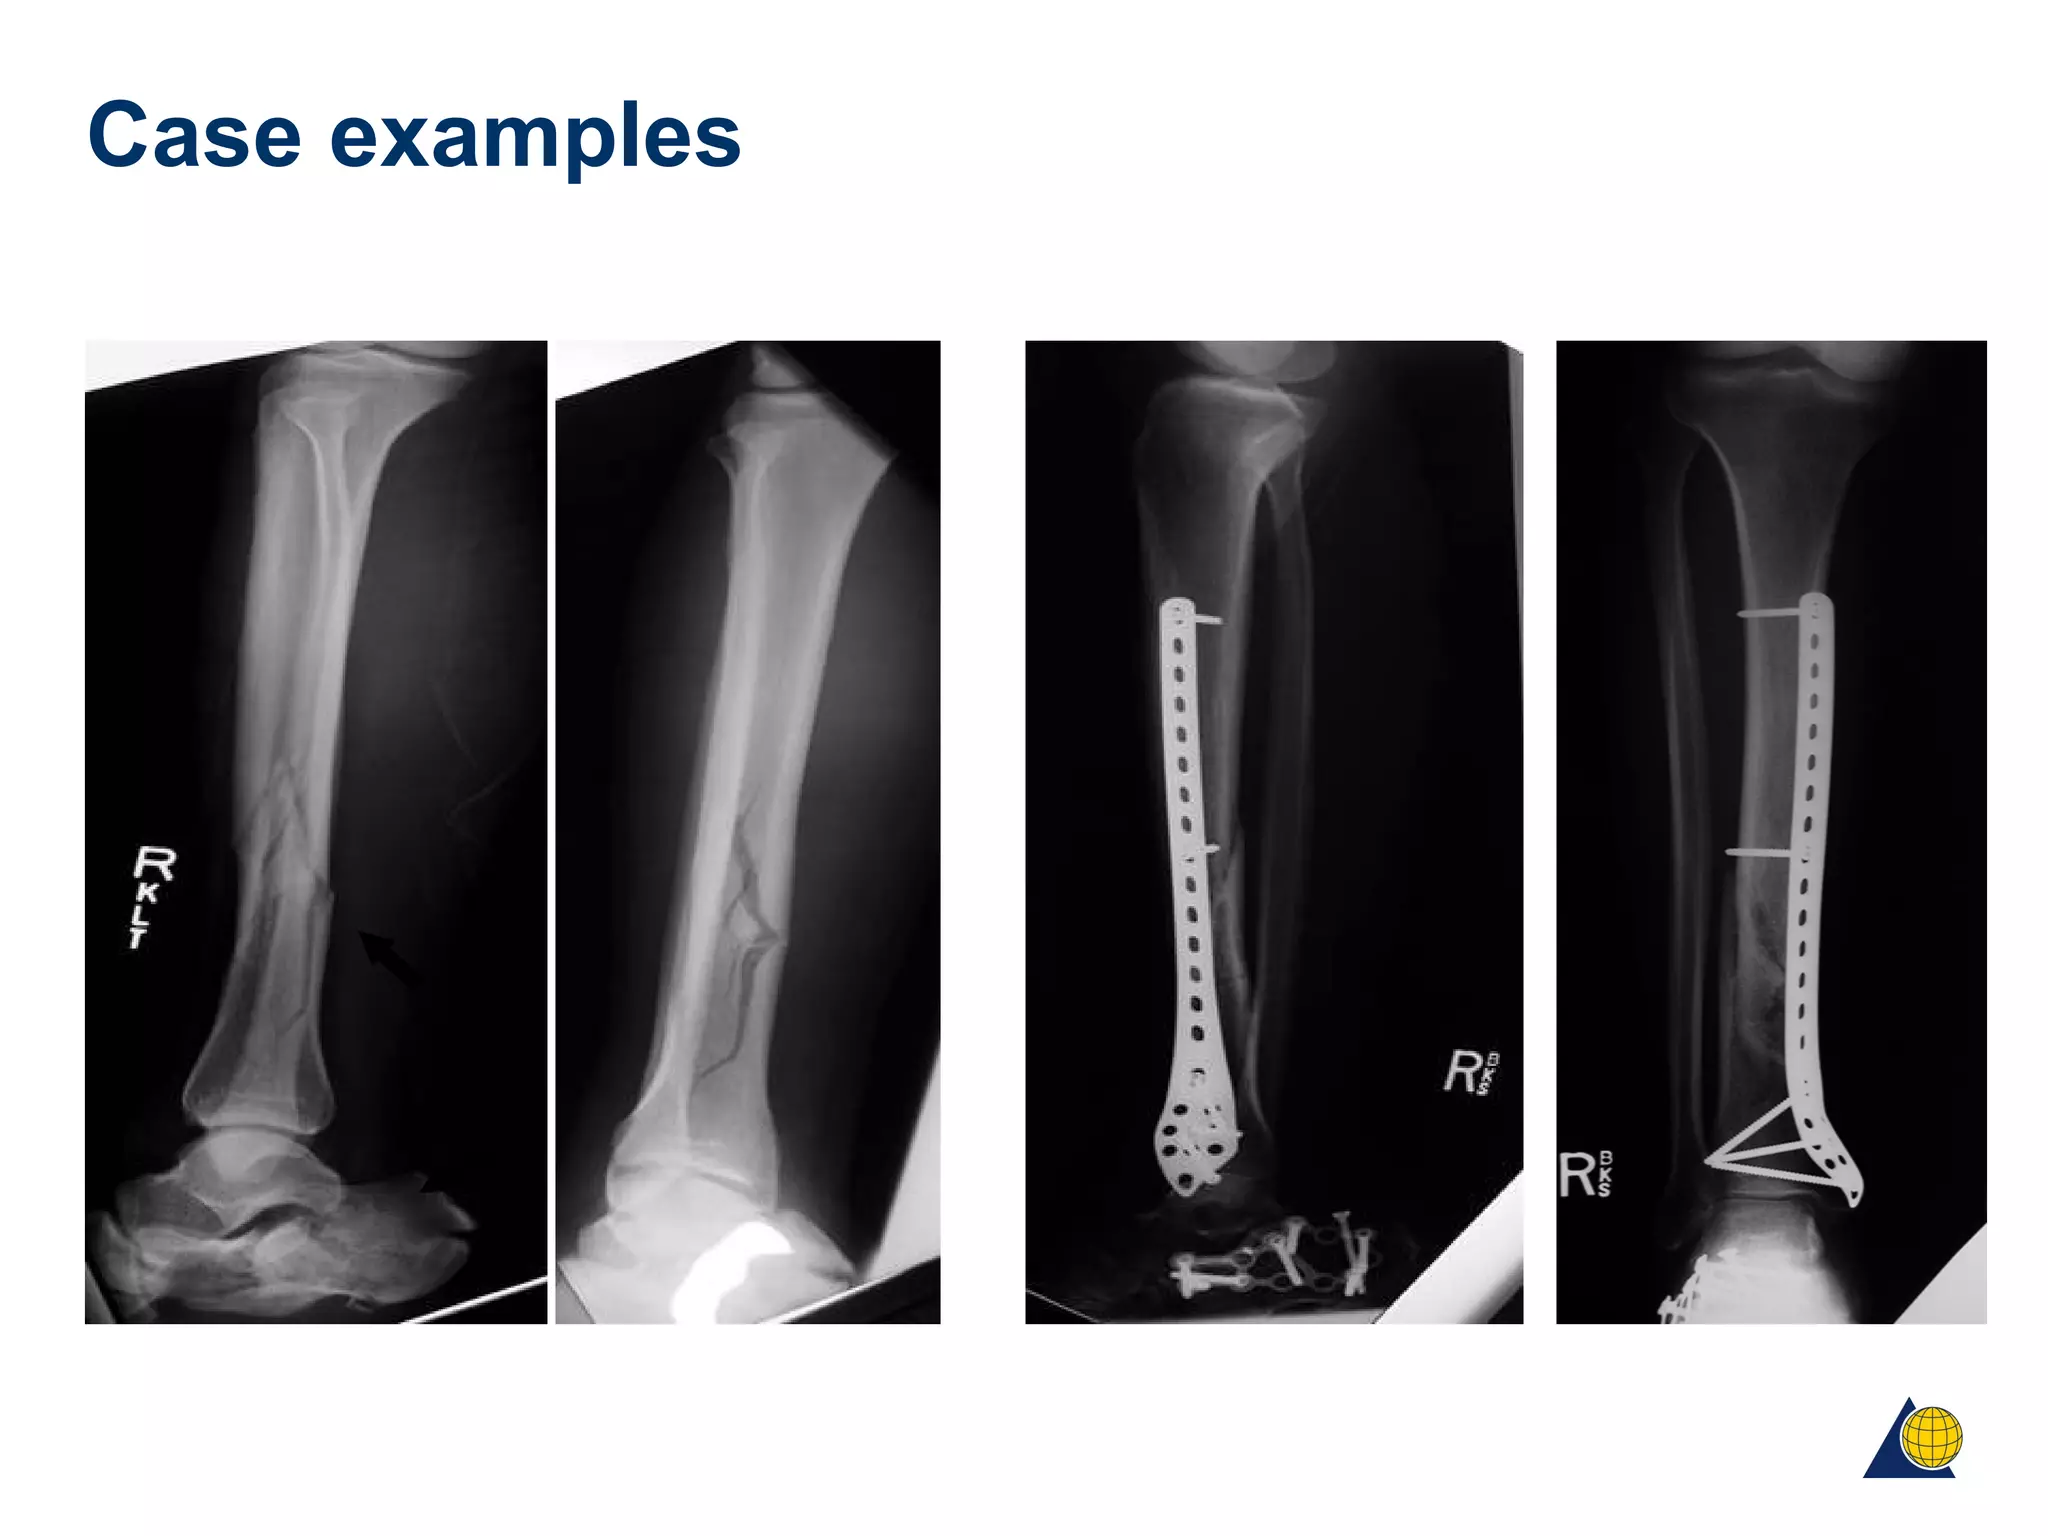

Case examples

Postoperatively 2 weeks 4 months